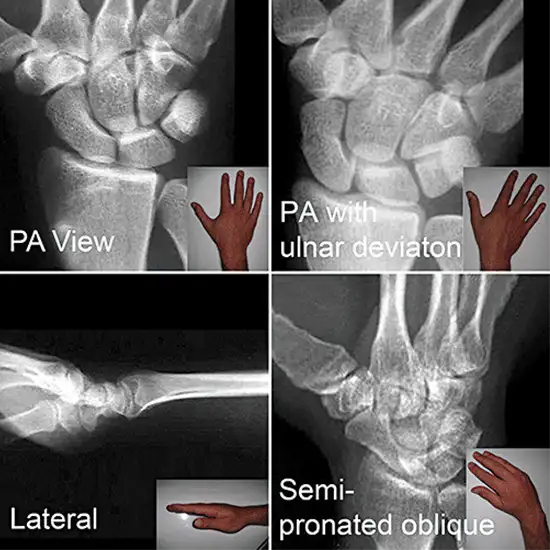

X-ray Left Scaphoid AP, LAT & Oblique Views

An X-ray of the scaphoid is a safe and painless procedure to visualize the scaphoid bone (a boat-shaped bone), which forms the wrist joint and seven other minor bones (also known as the carpal bone). The scaphoid is the most often fractured wrist bone.